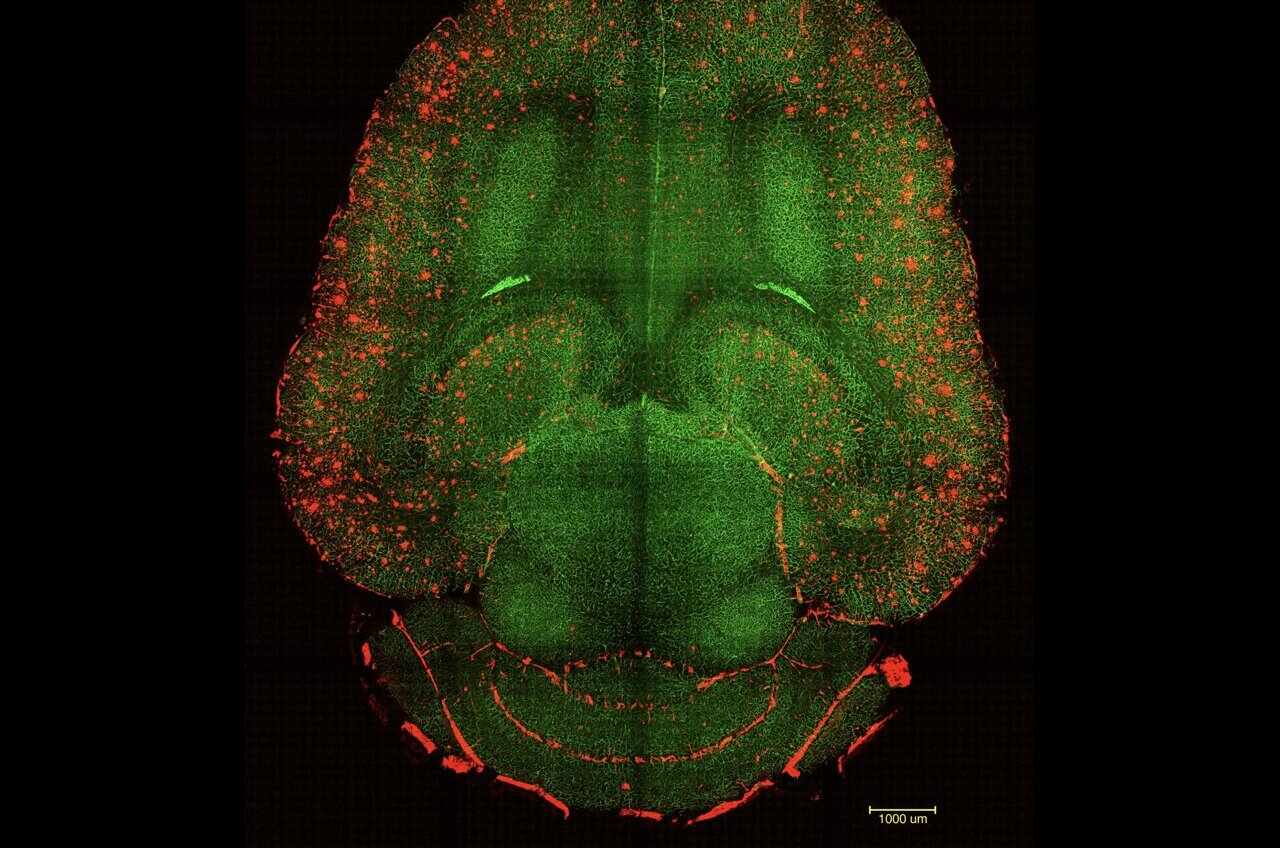

What makes this therapy stand out is its focus on restoring the blood-brain barrier (BBB), the crucial barrier that protects the brain, rather than directly targeting neurons. By enhancing the functionality of this barrier, researchers have reversed the pathological effects of Alzheimer’s in their animal subjects.

The blood-brain barrier is essential for shielding the brain from harmful pathogens or toxins that can enter through the bloodstream. This clever research targeted a specificmechanism that allowed harmful “waste proteins” to exit the brain through the BBB and enter the bloodstream for removal. For patients suffering from Alzheimer’s, the major culprits are proteins known as amyloid-β (Aβ), whose buildup negatively affects neurons.

“We believe the long-lasting effects stem from the restoration of the brain’s vascular network,” said Giuseppe Battaglia, group leader in the study and ICREA Research Professor at IBEC. He explained that toxic proteins like Aβ trigger disease advancement, but improved vascular functions lead to clearing away these toxins undone, letting the whole brain recover balance.

In light of cognitive decline from Alzheimer’s, it’s significant that the commonly inefficient system for clearing Aβ in also comes into play here. Under regular conditions, a protein called LRP1 works as a gatekeeper, helping move Aβ out of the brain through the bloodstream, but if it gets too overwhelmed, or not activated enough, Aβ starts to accumulate again, ensuing cognitive issues.

The cool supramolecular drugs from this team work by effectively triggering this gatekeeping system. By mimicking the elements LRP1 needs, they can help shuttle Aβ out of the brain, effectively restoring the vascular system’s role as a filtering pathway.